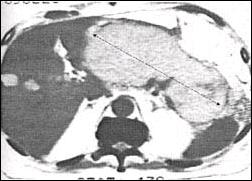

The diagnostic method prior to endoscopic drainage includes the clinical examination, laboratory findings, abdominal sonography, computed tomography (CT), magnetic resonance imaging(MRI) and endoscopic retrograde cholangiopancreatography(ERCP). Most of the pseudocysts were detected by means of sonography. The mean size of the cysts was 8,9 cm (range 6-21 cm) (Fig.1).

Fig. 1. CT scan showing the large pancreatic pseudocyst

(21 cm)